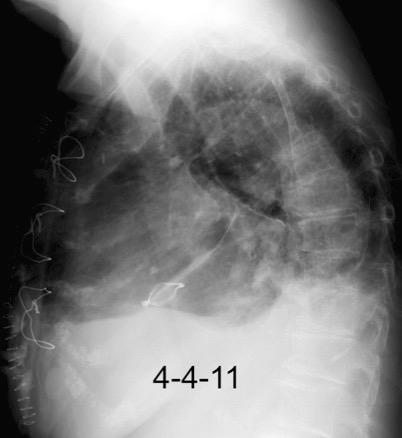

30 años

Borramiento de la banda PARA-aórtica por AdenoCa. de LII, no visible en 2005

Colapso de LII. TC: secreciones bronquiales.

Endoscopia tapón mucopurulento extraído

Borramiento parcial por Ca. epidermoide.